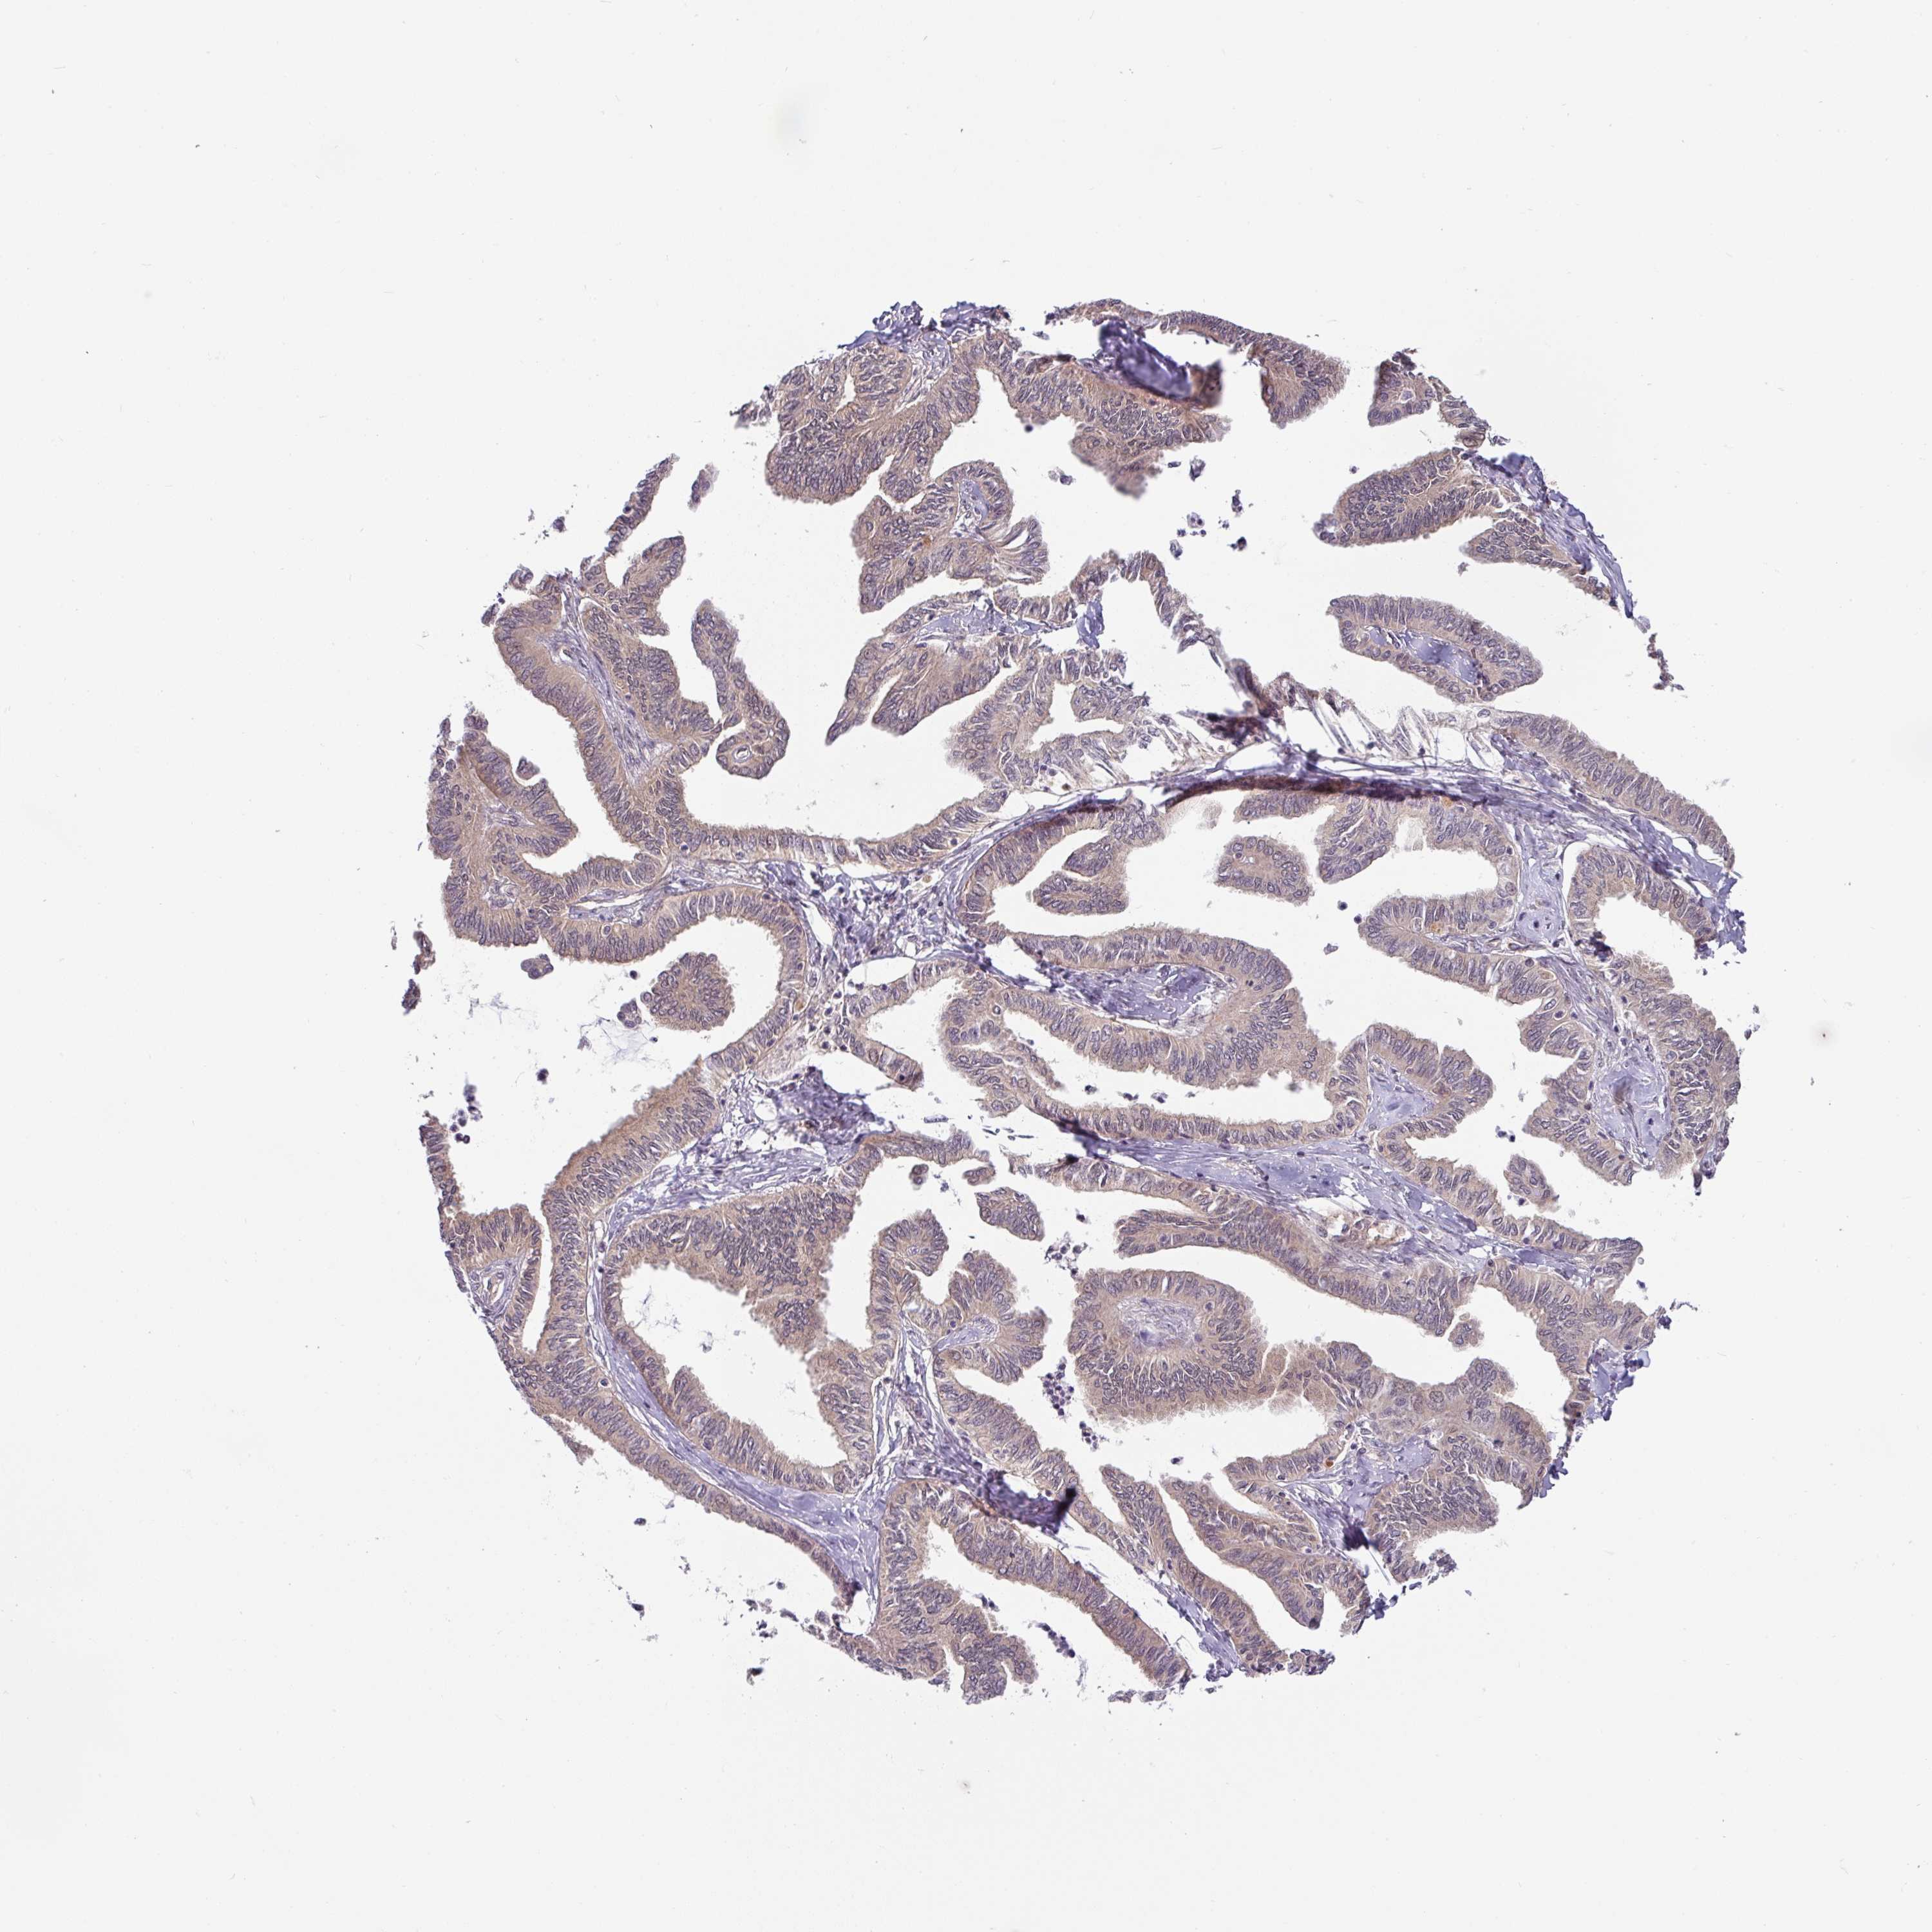

OVARIAN CANCER - Protein expressioni

A mouse-over function shows sample information and annotation data. Click on an image to view it in a full screen mode. Samples can be filtered based on level of antibody staining by selecting one or several of the following categories: high, medium, low and not detected. The assay and annotation is described here.

Note that samples used for immunohistochemistry by the Human Protein Atlas do not correspond to samples in the TCGA dataset.

Antibody stainingi

Antibody staining in the annotated cell types in the current human tissue is reported as not detected, low, medium, or high, based on conventional immunohistochemistry profiling in selected tissues. This score is based on the combination of the staining intensity and fraction of stained cells.

Each image is clickable and will lead to virtual microscopy that enables deeper exploration of all samples and also displays staining intensity scores, fraction scores and subcellular localization as well as patient and tissue information for each sample.

Antibody HPA049911

Antibody CAB010161

Cystadenocarcinoma, serous, NOS

Cystadenocarcinoma, mucinous, NOS

Adenocarcinoma, NOS

Carcinoma, endometroid

Carcinoma, NOS